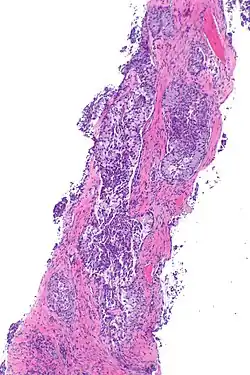

| Micrograph showing ALK positive lung adenocarcinoma. H&E stain. | |